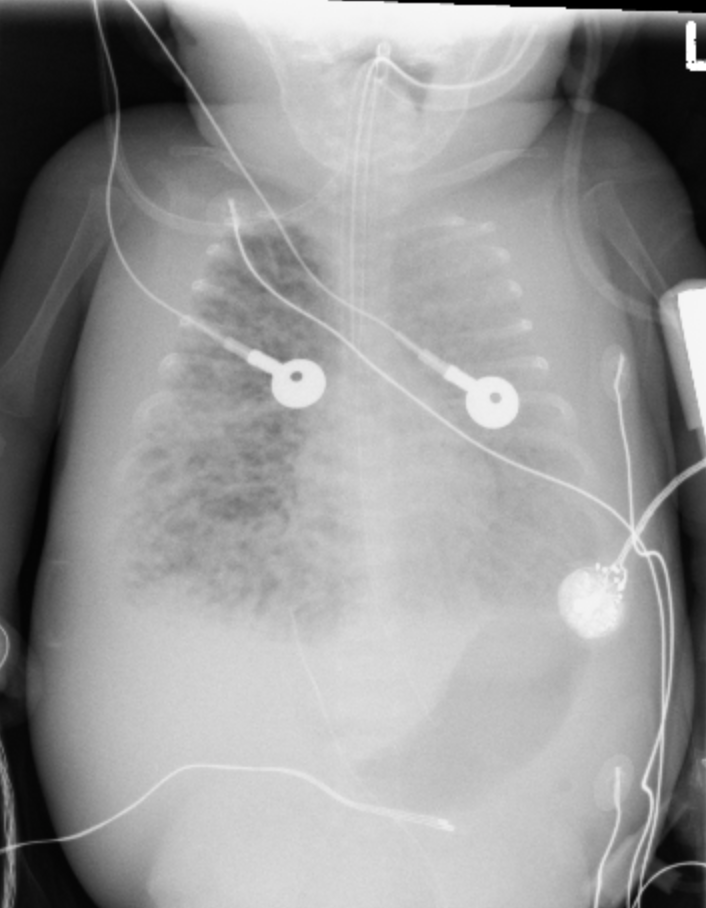

Bronchopulmonary Dysplasia

• Seen in premature babies, >3-4 weeks after birth (>4 weeks old give/take)

• Lungs damaged by prolonged mechanical ventilation

• Trach is a good clue

• Coarse markings with intermixed bubbly lucencies

• Markings gradually decrease over years

• Wilson-Mikity = BPD but no hx of mechanical ventilation